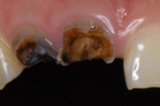

保険適用で白い詰め物を使用するには、治療部位や症例に関する一定の制約があります。具体的には、患者が虫歯の治療を必要としている部位が、目立つ前歯であることが大前提となります。また、治療の程度が「軽度から中等度の虫歯」である必要があり、重度の虫歯では適用されないこともあります。

- 治療:虫歯を除去した後、白い詰め物を装着します。